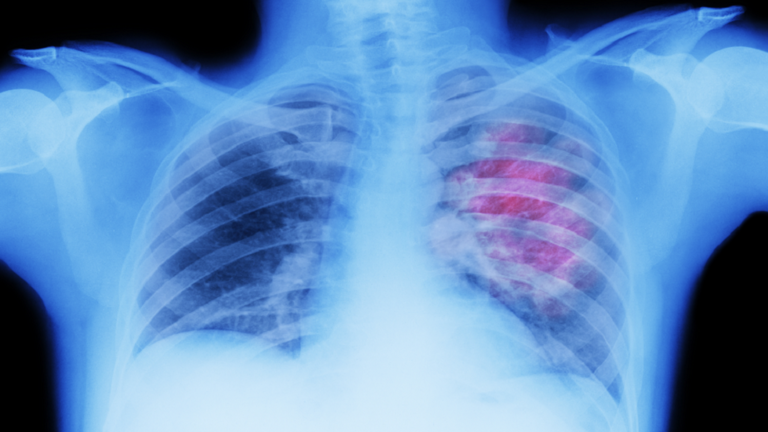

علامات لسرطان الرئة يمكن رؤيتها على الوجه!

حذر خبراء من أن تورم الوجه قد يكون علامة رئيسية على الإصابة بسرطان الرئة.

ويمكن أن يحدث تورم الوجه، على الرغم من أن هذا السبب أقل شهرة، عندما يمارس الورم ضغطا على الوريد الأجوف العلوي (SVC)، الذي يربط الرأس بالقلب. وتجعل الجدران الرقيقة لهذا الوريد الحيوي عرضة للضغط.

ووفقا لـ Macmillan Cancer Support، فإن معظم حالات انسداد الوريد الأجوف العلوي (SVCO) ناتجة عن سرطان الرئة.

وبالإضافة إلى تورم الوجه، قد يعاني الأفراد أيضا من تورم في الرقبة والذراعين وأعلى الصدر بسبب ضغط الوريد. وقد تشمل الأعراض المصاحبة الأخرى ضيق التنفس، أو الصداع، أو تغيرات في البصر، أو ظهور أوردة زرقاء على الصدر، أو الدوخة.